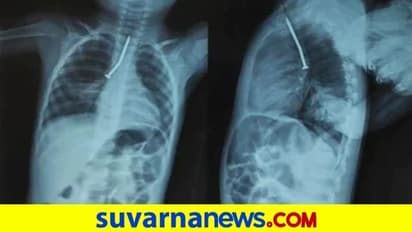

ಕೋಲ್ಕತ್ತಾ(ಮಾ.19): ಎರಡು ವರ್ಷ ಪ್ರಾಯದ ಬಾಲಕನೋರ್ವ ಕಬ್ಬಿಣದ ಮೊಳೆಯನ್ನು ಆಕಸ್ಮಿಕವಾಗಿ ನುಂಗಿದ್ದು, ಕೂಡಲೇ ಅಸ್ವಸ್ಥನಾದ ಈ ಬಾಲಕ ವೈದ್ಯರ ಶಸ್ತ್ರಚಿಕಿತ್ಸೆಯಿಂದಾಗಿ ಪವಾಡ ಸದೃಶವಾಗಿ ಪಾರಾಗಿದ್ದಾನೆ. ಪಶ್ಚಿಮ ಬಂಗಾಳದ (West Bengal) ಉತ್ತರ ದಿನಾಜ್‌ಪುರ (North Dinajpur) ಜಿಲ್ಲೆಯಲ್ಲಿ ಈ ಘಟನೆ ನಡೆದಿದೆ.

ಎರಡು ವರ್ಷದ ಮುಸ್ತಾಕಿನ್ ಅಲಿ (Mustakin Ali) ಎಂಬ ಮಗುವೇ ಹೀಗೆ ಕಬ್ಬಿಣದ ಮೊಳೆ(Iron Nail) ನುಂಗಿ ಅಪಾಯದಿಂದ ಪಾರಾದ ಬಾಲಕ. ಮಗುವಿನ ಅಜ್ಜ ಮನೆಯ ಹೊರಗೆ ಬಿದಿರು ಕತ್ತರಿಸುತ್ತಿದ್ದಾಗ ಮುಸ್ತಾಕಿನ್ ಅವರ ಬಳಿ ಆಟವಾಡುತ್ತಿದ್ದ. ಈವೇಳೆ ಇದ್ದಕ್ಕಿದ್ದಂತೆ, ಮಗು ತೀವ್ರವಾಗಿ ಕೆಮ್ಮುವುದು ಮತ್ತು ಬಾಯಿಯಿಂದ ರಕ್ತಸ್ರಾವವಾಗುವುದನ್ನು ಅಜ್ಜ ನೋಡಿದರು. ಮಗು ಮುಸ್ತಾಕಿನ್ ಸ್ಥಿತಿ ಅವರ ಮನೆಯವರಲ್ಲಿ ಭಯವನ್ನು ಉಂಟುಮಾಡಿತು. ಕೂಡಲೇ ಕುಟುಂಬದವರು ಅವರನ್ನು ರಾಯ್‌ಗಂಜ್ ವೈದ್ಯಕೀಯ ಕಾಲೇಜಿಗೆ (Raiganj Medical College) ಕರೆದೊಯ್ದರು.

ಅಷ್ಟರಲ್ಲಾಗಲೇ ಮಗುವಿಗೆ ಉಸಿರಾಟದ ತೊಂದರೆ ಕಾಣಿಸಿಕೊಂಡಿದ್ದು, ನಿರಂತರವಾಗಿ ವಾಂತಿ ಮಾಡಿಕೊಳ್ಳುತ್ತಿತ್ತು. ರಾಯಗಂಜ್‌ ಮೆಡಿಕಲ್ ಕಾಲೇಜಿನಿಂದ, ಮುಸ್ತಾಕಿನ್ ಅವರನ್ನು ನಂತರ ಮಾಲ್ಡಾ ವೈದ್ಯಕೀಯ ಕಾಲೇಜಿಗೆ (Malda Medical College) ದಾಖಲಿಸಲಾಯಿತು. ಅಲ್ಲಿಂದ ಅವರನ್ನು ಮತ್ತೆ ಕೋಲ್ಕತ್ತಾದ SSKM ಆಸ್ಪತ್ರೆಗೆ ವರ್ಗಾಯಿಸಲಾಯಿತು. ಭಾನುವಾರ ಎಸ್‌ಎಸ್‌ಕೆಎಂ ಆಸ್ಪತ್ರೆಯಲ್ಲಿ ವೈದ್ಯರು ಹಲವು ಗಂಟೆಗಳ ಕಾಲ ಶಸ್ತ್ರಚಿಕಿತ್ಸೆ ನಡೆಸಿ ಅವರ ಗಂಟಲಿನಲ್ಲಿ ಸಿಲುಕಿದ್ದ ಕಬ್ಬಿಣದ ಮೊಳೆಯನ್ನು ಹೊರತೆಗೆಯುವಲ್ಲಿ ಯಶಸ್ವಿಯಾಗಿದ್ದಾರೆ. ಸದ್ಯ ಮಗು ಐಸಿಯುನಲ್ಲಿದ್ದು,  ಚೇತರಿಸಿಕೊಳ್ಳುತ್ತಿದೆ.

SSKM ಆಸ್ಪತ್ರೆಯ ಪ್ರಕಾರ, ಬಾಲಕ ಮುಸ್ತಾಕಿನ್ ಗೆ ಭಾನುವಾರ ಬೆಳಗ್ಗೆ 7 ಗಂಟೆಗೆ  ಶಸ್ತ್ರಚಿಕಿತ್ಸೆ ನಡೆಸಿ ವೈದ್ಯರು ಪ್ರಾಣ ಉಳಿಸಿದ್ದಾರೆ. ಅರುಣವ್ ಸೇನ್‌ಗುಪ್ತಾ (Arunav Sengupta) ನೇತೃತ್ವದಲ್ಲಿ 4 ವೈದ್ಯರ ತಂಡ ಅವರಿಗೆ ಬಾಲಕನಿಗೆ ಶಸ್ತ್ರಚಿಕಿತ್ಸೆ ನಡೆಸಿದರು. ಮಗುವಿನ ಶ್ವಾಸನಾಳದಲ್ಲಿ ಮೊಳೆ ಸಿಕ್ಕಿ ಹಾಕಿಕೊಂಡಿದ್ದರಿಂದ ಮಗುವಿಗೆ ಉಸಿರಾಟದ ತೊಂದರೆ ಮತ್ತು ವಾಂತಿಯಾಗುತ್ತಿತ್ತು ಎಂದು ವೈದ್ಯರು ಹೇಳಿದರು.